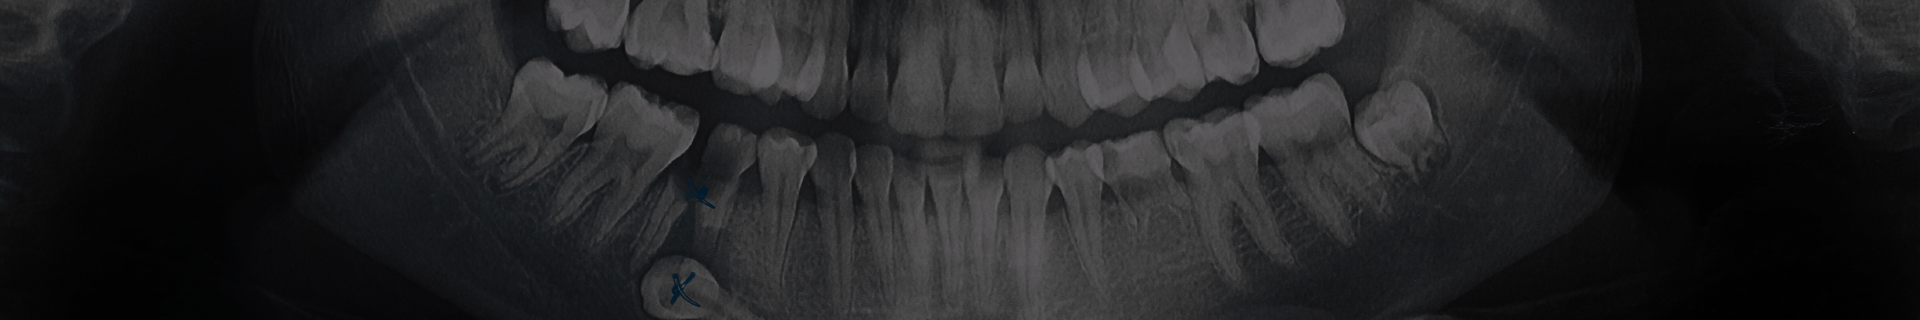

- Radiografia panoramică: Ideală pentru o vizualizare completă a dinților, maxilarelor și articulațiilor temporo-mandibulare. Este utilizată frecvent pentru planificarea tratamentelor ortodontice și implantologice.

- CBCT (Tomografie computerizată cu fascicul conic): Această tehnologie avansată oferă imagini tridimensionale detaliate, fiind esențială în cazurile complexe, cum ar fi intervențiile chirurgicale, tratamentele endodontice și implantologia.